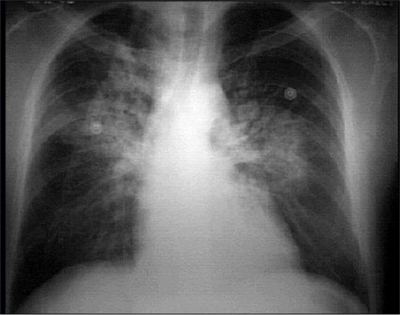

This is our patient's PA chest X ray

Click on the xray to enlarge it.

Choose the best interpretation of the chest X ray in our patient:

Increased pulmonary vascularity +dilated pulmonary trunk

Pulmonary infiltrate

Dilated left atrium

Pulmonary edema

Pleural effusion